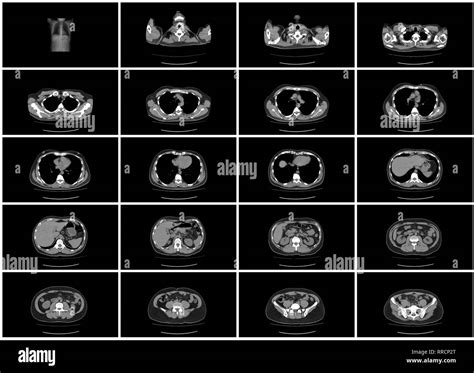

When a physician suspects an underlying issue within the digestive or urinary systems, a CT scan abdomen is often the first imaging modality recommended to gain a clear, detailed picture of the internal anatomy. This diagnostic procedure, formally known as a computed tomography scan, utilizes X-ray technology paired with sophisticated computer processing to create cross-sectional images of the organs, blood vessels, and soft tissues located in the abdominal cavity. Because it offers a comprehensive view that standard X-rays cannot match, it is an invaluable tool for diagnosing a wide range of conditions, from unexplained pain to complex tumor staging.

The primary goal of a CT scan abdomen is to provide a precise anatomical map of the abdominal area, which includes organs like the liver, gallbladder, spleen, pancreas, kidneys, and intestines. Unlike a simple X-ray, which produces a flat, two-dimensional image, a CT scan creates slices that allow doctors to visualize these organs in three dimensions. This is crucial for identifying structural abnormalities, infections, or growths.